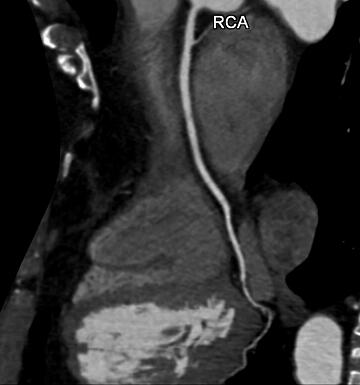

Darstellung der rechten Herzkranzarterie bei einem Mitte Sechzig Jahre alten Mann. Unspezifische Symptome führten zu der CT Untersuchung. Es zeigen sich erhebliche Fettablagerungen (dunkle Stellen) mit deutlichen Einengungen.